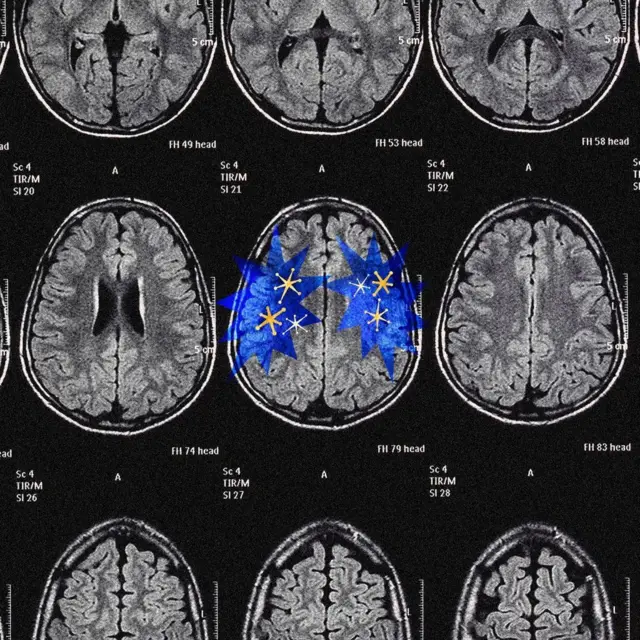

Buna ödül sistemi deniyor ve dopamin de kararlarımıza ve motivasyonlarımıza rehberlik ederken kullandığı başlıca araç.

Hem müthiş akıllı hem de korkutucu şekilde şeytanı bir araç. Dopamin bizi ileri götürmeye devam eden şey.

Kaynak, Serenity Strull